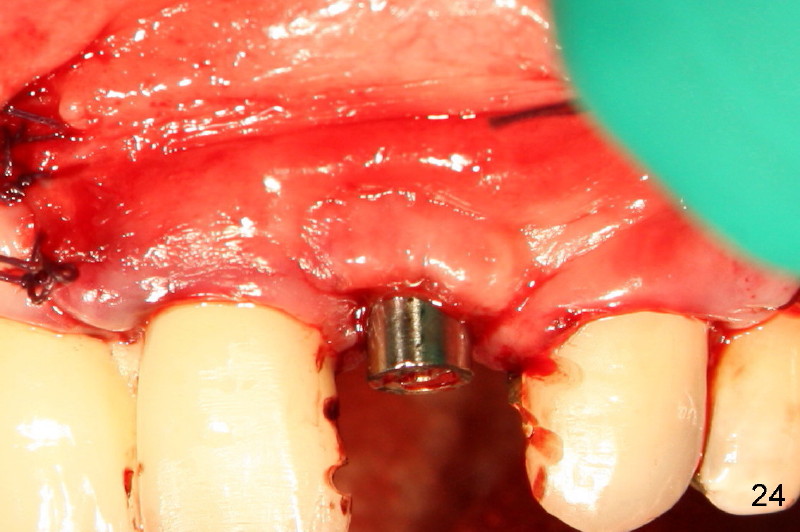

Segmental Osteotomy for Misplaced Implant

This corrective surgery was performed by Dr. Bernee Dunson.

Xin Wei, DDS, PhD, MS 1st edition 12/21/2011, last revision 12/23/2011